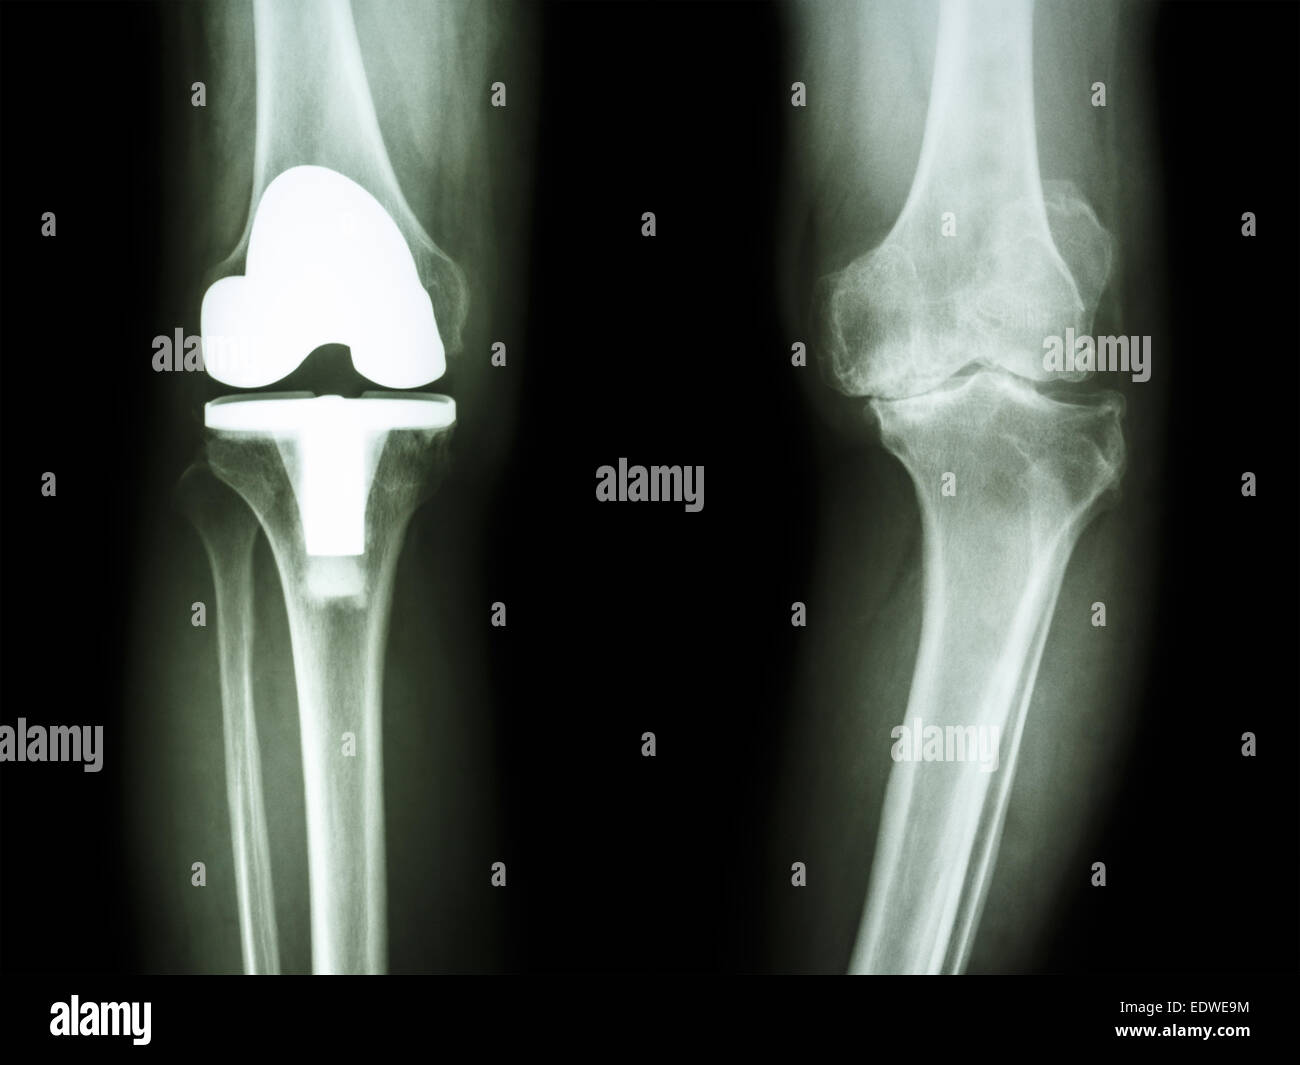

Film x-ray de l'arthrose du genou genou articulation artificielle et patient Banque D'Imageshttps://www.alamyimages.fr/image-license-details/?v=1https://www.alamyimages.fr/photo-image-film-x-ray-de-l-arthrose-du-genou-genou-articulation-artificielle-et-patient-77392048.html

Film x-ray de l'arthrose du genou genou articulation artificielle et patient Banque D'Imageshttps://www.alamyimages.fr/image-license-details/?v=1https://www.alamyimages.fr/photo-image-film-x-ray-de-l-arthrose-du-genou-genou-articulation-artificielle-et-patient-77392048.htmlRFEDWE9M–Film x-ray de l'arthrose du genou genou articulation artificielle et patient